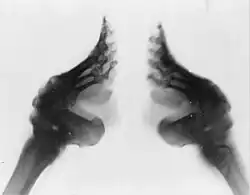

Krępowanie (bandażowanie) stóp – chiński zwyczaj kultywowany od ok. X do początków XX wieku, polegający na bandażowaniu stóp dziewcząt, celem ich skrócenia i deformacji prowadzących do pożądanego efektu estetycznego. Krępowanie stosowano początkowo u dziewcząt z wyższych klas społecznych, od których nie wymagano wykonywania intensywnych prac fizycznych. Obyczaj, który był wyznacznikiem statusu społecznego, przyjął się z czasem również wśród klas niższych. Za czasów ostatniej dynastii, Qing (1644–1912), rozpowszechniony był wśród wszystkich warstw społecznych, szczególnie na północy kraju. Krótkie stopy były w Chinach symbolem wytworności i zapewniały właścicielce dobre zamążpójście. Krępowanie miało także podtekst erotyczny, na co zwrócił uwagę również Zygmunt Freud, dostrzegając w nim fetyszyzm.

Krępowanie polegało na owijaniu stóp bandażem, tak aby zagiąć palce – z wyjątkiem wielkiego – w kierunku pięty, co doprowadzało do złamania kości śródstopia.

Zabieg zaczynano u dziewcząt w wieku 5–12 lat. Stopy owijano bardzo ciasno bandażem, a dziewczynie podawano dietę, która miała wywołać zmiękczenie kości, co ułatwiało złamanie i deformację. Bandaż co tydzień owijano ciaśniej. Krępowanie było źródłem wielkiego bólu. Chińskie przysłowie mówi: Piękność wymaga cierpienia; każda para zabandażowanych stóp kosztuje wannę łez[2]. Powstające na skutek złamania otwarte rany niosły ryzyko zakażenia i powikłań. Szacuje się, że umierało od nich co najmniej 10 procent dziewcząt.

Stopy trzeba było owijać bandażem do końca życia. Jeżeli zabieg wykonano niepoprawnie, były one dla właścicielki źródłem przewlekłego bólu. Czasem zabieg wywoływał częściowy paraliż lub zanik mięśni (atrofię). Kiedy w komunistycznych Chinach pod groźbą śmierci nakazano kobietom zrezygnować z krępowania, stopy niektórych z nich urosły o kilka centymetrów.